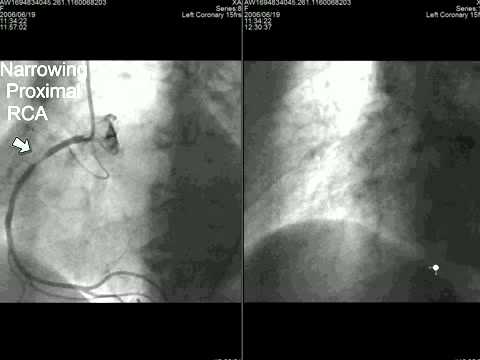

Coronary Angiogram Full Length Procedure Youtube